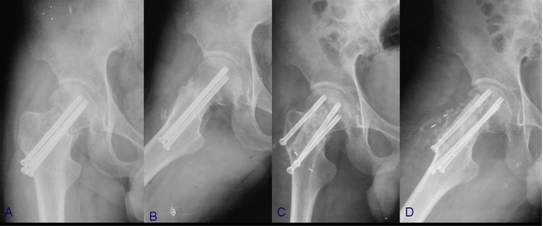

骨折端充分显露后,可直视下清理骨折端至新鲜断面,通过牵引、内旋下肢间接复位或撬拨骨折端直接复位,随后多枚克氏针临时固定,透视下见骨折端复位满意后进行最终的内固定,股骨颈骨折可采用多枚平行拉力螺钉或锁定钢板,同时行吻合血管的游离腓骨移植(图5),粗隆间骨折可根据其骨折类型选用锁定钢板或髓内钉,通常无需植骨(图6)。

图6 股骨粗隆间骨不连病例

A,  患者术前X线(内固定术后3月);B,采用前侧入路髓内钉翻修术后